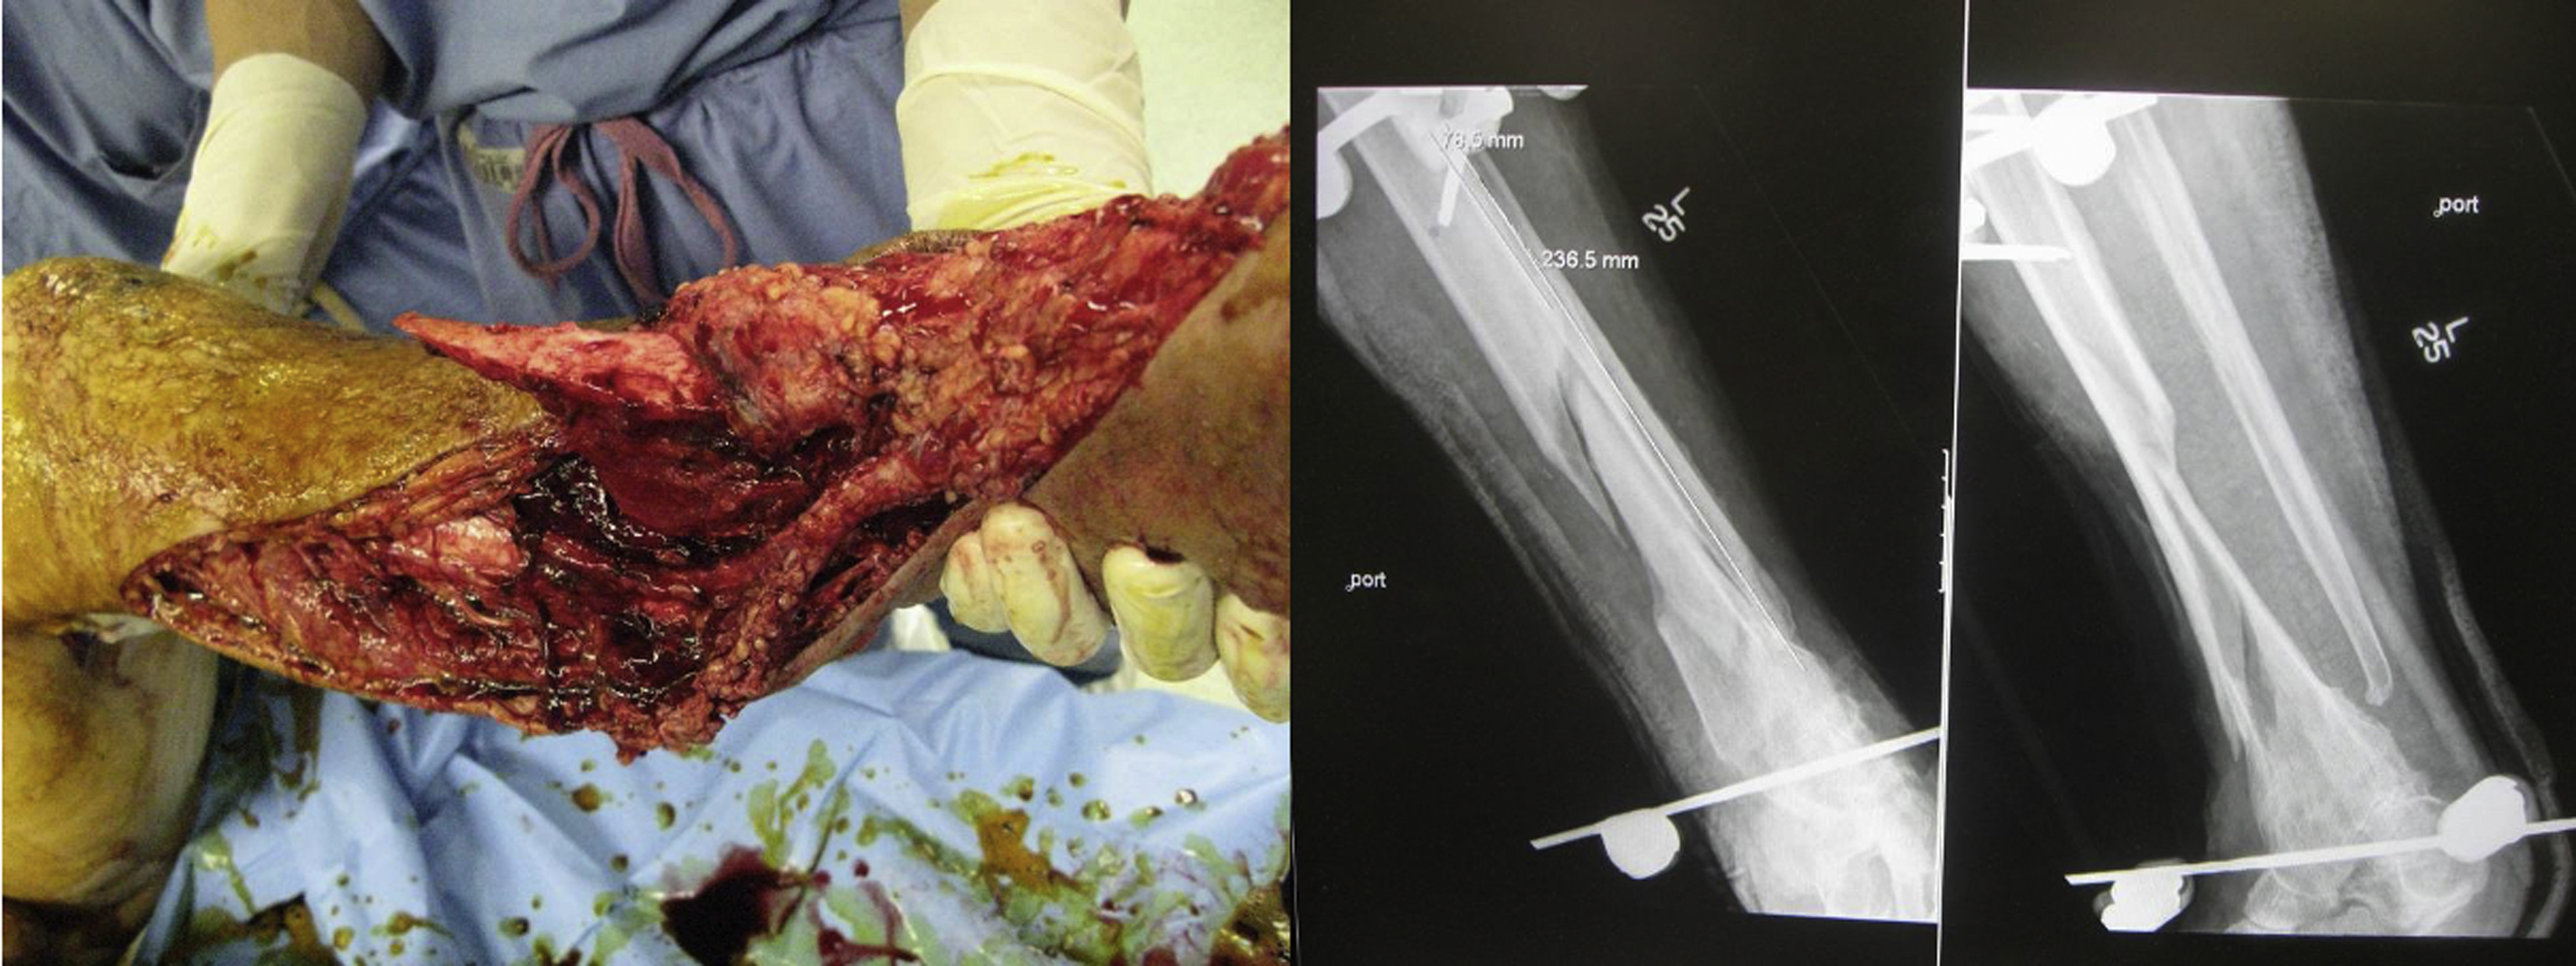

A 33-year-old man sustained a right lower extremity Gustilo IIIC injury following a motorcycle crash. He initially underwent revascularization of his anterior tibial artery using a reverse saphenous vein graft ( Fig. 2 ). He was also noted to have transection of his tibial nerve with a 10 cm gap, comminuted distal tibial and fibular shaft fractures, disruption of the Achilles tendon, and 30 cm by 15 cm soft tissue defect ( Fig. 3 ). After 2 debridements, in a joint procedure with orthopedic surgery he underwent open reduction and internal fixation of the right tibia, tibial nerve reconstruction with sural nerve cable grafting, Achilles tendon reconstruction with vascularized tensor fascia lata and iliotibial band, and soft tissue coverage with a left anterolateral thigh flap and split-thickness skin grafts ( Fig. 4 ). The anterolateral thigh flap was anastomosed end to end to the disrupted posterior tibial artery, and 2 venous anastomoses were performed using 3.0 and 2.0 venous couplers, respectively. The left thigh donor site and the lateral foot were then skin grafted to complete the reconstruction.